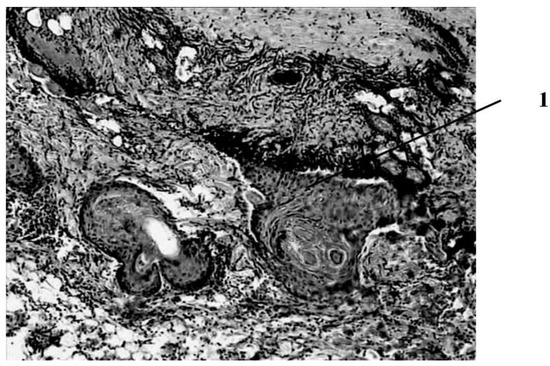

Seven days after the burn, in animals that had a wound punctured daily with a gas mixture with ozone, the scab partially separates from the wound surface as a result of penetration of a growing layer of epidermis under it (Figure 4).

This is the marginal epithelization of the wound, in which the proliferating epithelium of the deep sections of the hair follicles preserved in the lower layers of the dermis also takes part. The separation of the scab follows the line of a clearly expressed solid leukocyte demarcation shaft. In the center of the wound bottom, necrosis of the skin’s own muscle is noted for its entire thickness and infiltration of necrotized muscle fibers by leukocytes. In the muscle layer located to the periphery of its necrosis zone, there are phenomena of muscle fiber regeneration in the form of proliferation of myocyte nuclei and neoplasm of thin muscle fibers with basophilic cytoplasm. Under the layer of the skin’s own muscle, a hemorrhage site containing nonhemolysed erythrocytes is visible, and along its periphery there is fibroblast proliferation and manifestations of neoangiogenesis. Individual newly formed capillary-type vessels grow into the hemorrhage zone. There is also a pronounced proliferation of epithelium in the hair follicles located in the deep layers of the dermis. Thus, seven days after the burn, under conditions of pricking wounds with an ozone-containing gas mixture, more pronounced (compared to animals of other series) reparative processes are noted in the wounds in the form of more intense marginal epithelization, the formation of granulation tissue and the appearance of not only muscle kidneys, but also newly formed muscle fibers in the damaged own muscle layer of the skin (Figure 5).

Figure 4. Intensive proliferation of connective tissue cells in the adipose tissue surrounding the skin’s own muscle, the formation of new capillary-type vessels in rats treated with ozone–oxygen mixture (1—clusters of red blood cells, 2—newly formed microvessels). magn. ×400.

Figure 5. Results of histological examination of the wound seven days after the application of the burn with subcutaneous injection of an ozone–oxygen gas mixture. 1—proliferation of the epithelium of the preserved parts of the hair follicle bulbs. magn. ×100.